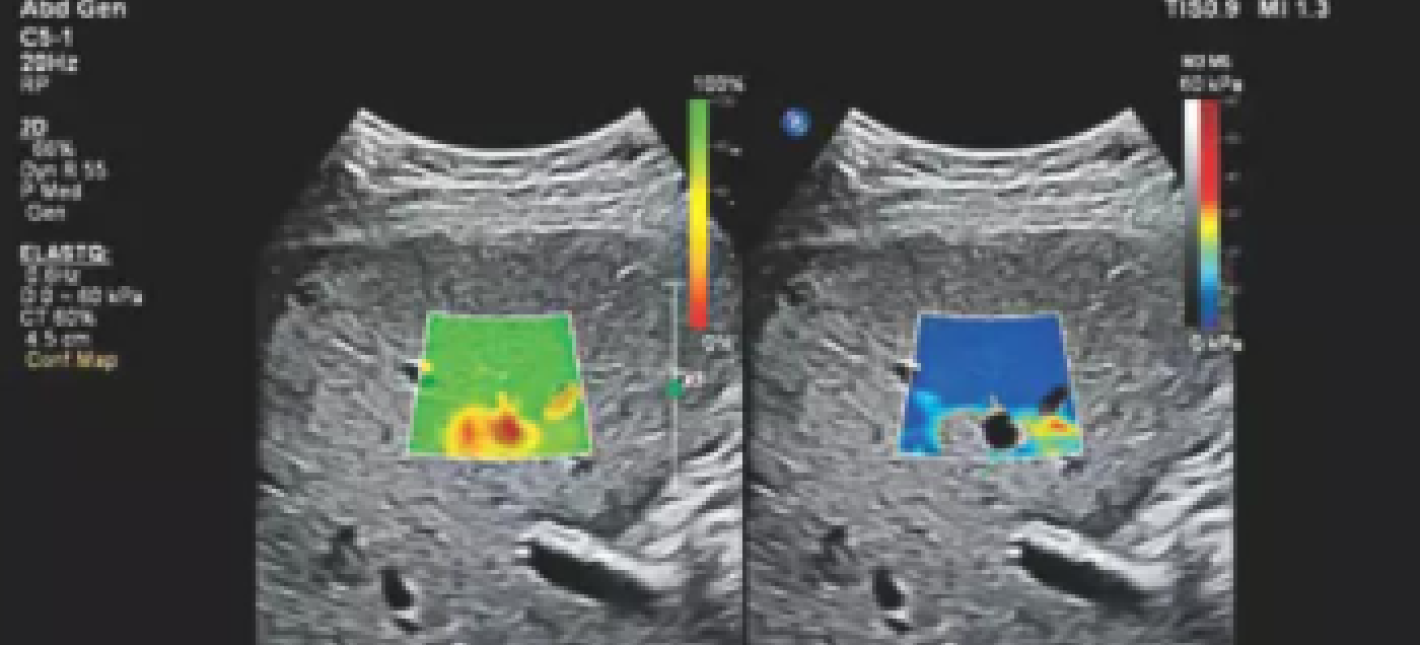

При лёгком надавливании датчиком оценивается, как ткань смещается под давлением. На экране формируется цветовая карта:

Такое цветовое картирование помогает врачу визуально определить подозрительные участки.